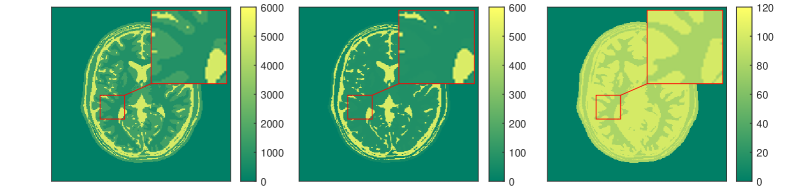

The results for each of the above mentioned algorithms can be found in Figures 3 and 4. We use the MRF reconstruction as initialization for the L-M algorithm, and compare that with the result of the BLIP algorithm when using a relatively refined dictionary. The advantage of integrated-physics approaches is evident by checking the reconstructions in Figure 3 as well as quantitatively by looking at the error maps in Figure 4. In this example, we have used a time series of the 1/8 Cartesian-subsampled k-space data (Fourier coefficients of magnetizations) of length 40. In the original MRF algorithm (typically requiring a large time series of k-space data), this test setting is far from yielding a reasonable result, while BLIP has improved a little by enforcing the projection to the Bloch manifold. But still one observes deficiencies. The method with integrated physics, however, appears to be efficient and it returns the best results among the three methods.

Here, is the projection operator onto the feasible set . The operator is the Frechét derivative of the parameter-to-solution map of the Bloch equations, and is the generalized inverse of the sub-sampled Fourier transform, i.e. , where is the zero filling operator, and is the inverse Fourier transform. For comparing a variety of algorithms for qMRI, we present a set of examples in the following. Our tests are based on synthetic data from an anatomical brain phantom, publicly available from the Brain Web Simulated Brain Database [24, 48, 119]. More details on how to generate this data can be found in [57] or [52].